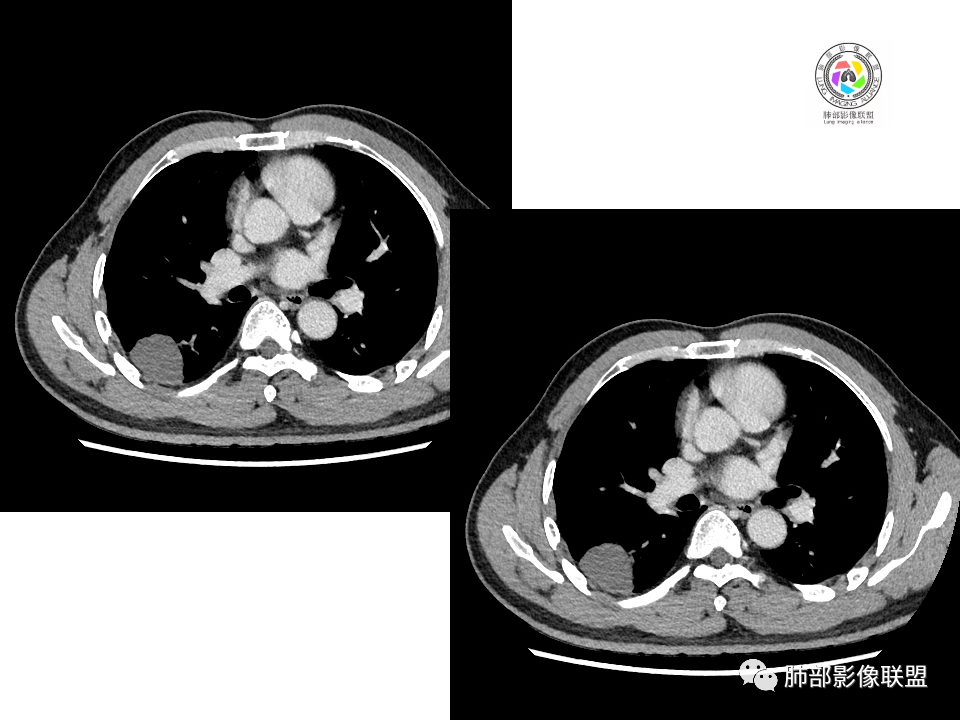

2.右肺下叶背段胸膜下块影,边界清楚光整,上下极见磨玻璃晕,未见明显分叶毛刺和棘状突起,未见胸膜凹陷或胸壁侵入。密度均匀,轻度不均匀强化。未见支气管进入。

3.右肺中叶外侧段胸膜下散在小片影,磨玻璃密度为主,边界不清,支气管相关。符合炎性特征!

4.右肺下叶基底段支气管血管束旁小结节影,边界清楚,强化不明显。注意,这结节在“遥远的”基底段。

显然本例焦点在于背段那个边缘光整的块影!

1.边缘光整干净,大病灶缺乏坏死等,不符合鳞癌影像学特征。尽管有吸烟史,还是偏年轻。

2.边缘光整,会是小细胞癌或是大细胞癌吗?小细胞癌的肺门纵隔淋巴结增大往往十分夸张,该患者不符合。

注意,基底段支气管血管束旁的小结节影,即便是淋巴结,也与背段病灶引流途径不符。